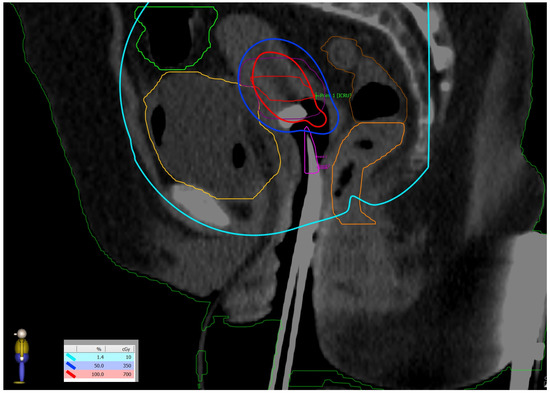

Figure 5.

Dose distribution: prescribed dose per fraction—7 Gy (red isoline)—covers more than 90% of the CTV high risk; 50% of the prescribed dose per fraction—3.5 Gy (blue isoline)—covers more than 99% of the CTV intermediate risk. The dose on the skin surface was 0 Gy from EBT.